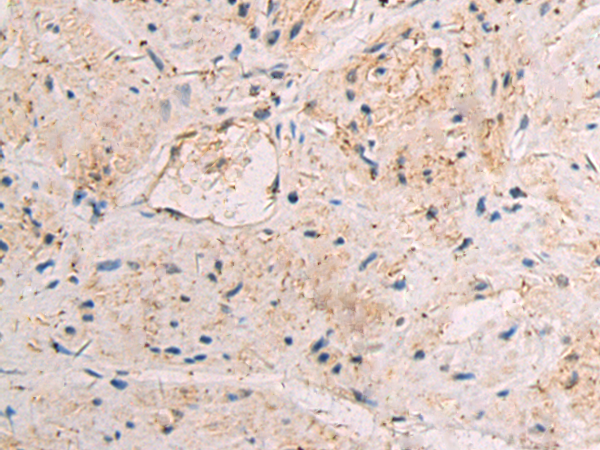

IHC |

IHC positive control: |

Human breast carcinoma tissue |

IHC Recommend dilution: |

50-100 |